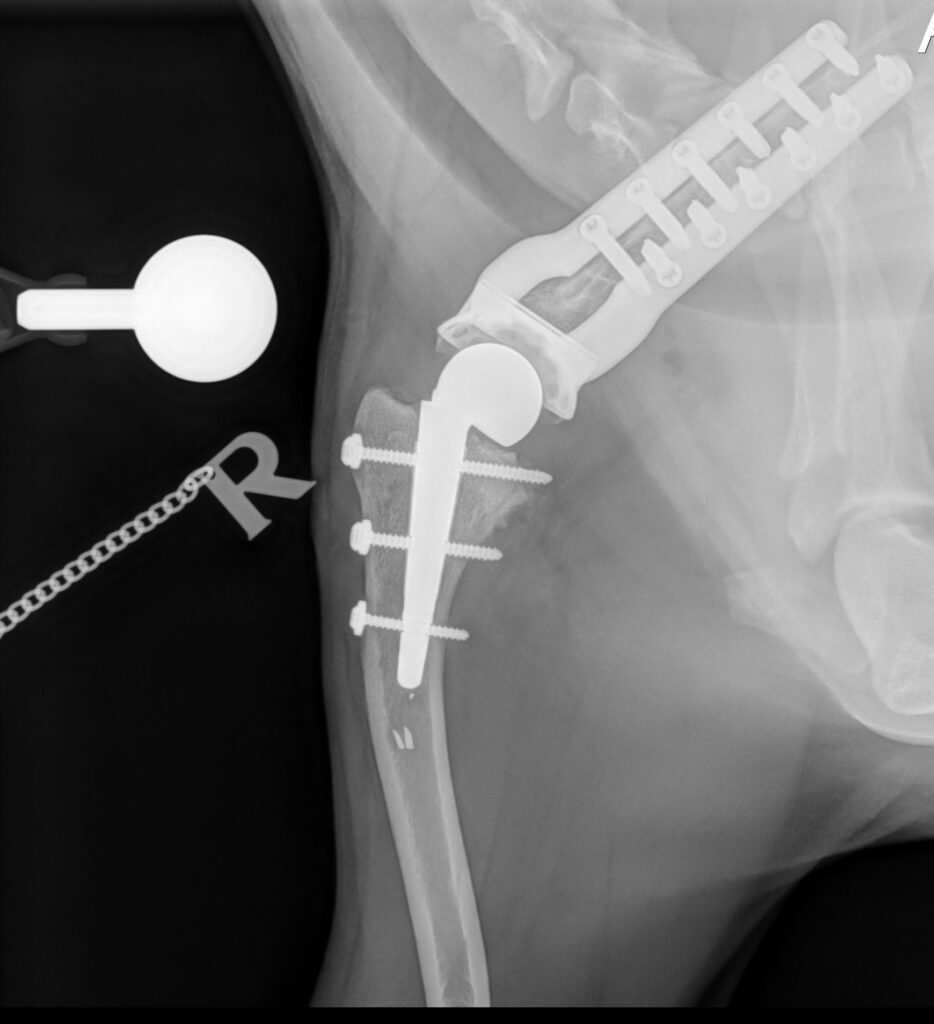

Limb sparing/salvage

Unique options to Fitzpatrick Referrals in limb sparing and salvage for treating trauma and cancer in the forelimb or hind limb.